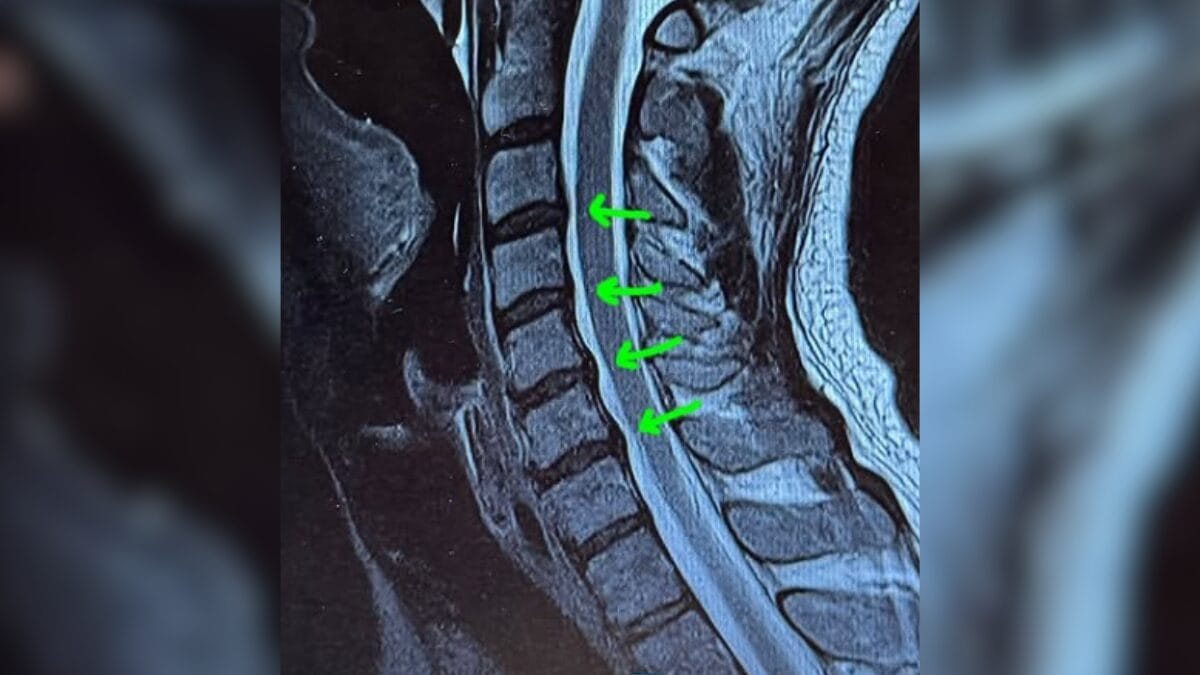

O cantor Tiago Iorc precisou ser internado às pressas neste sábado (11) após uma crise de hérnia de disco na região cervical, com uma “dor desconcertante”, conforme definiu o próprio artista em um anúncio feito nas redes sociais. Ele ainda fará um procedimento de bloqueio do processo inflamatório com injeções nas áreas afetadas da coluna, segundo o cantor.

Nas redes sociais, Tiago Iorc explicou que o problema vem de muitos anos de má-postura, “basicamente, por eu ficar com a cabeça baixa e o pescoço curvado por muito tempo”. Ele afirmou que teve uma crise parecida há quatro anos, ocasião em que a cirurgia já havia sido sugerida, mas que ele conseguiu contornar com tratamentos como fisioterapia, pilates e osteopatia.